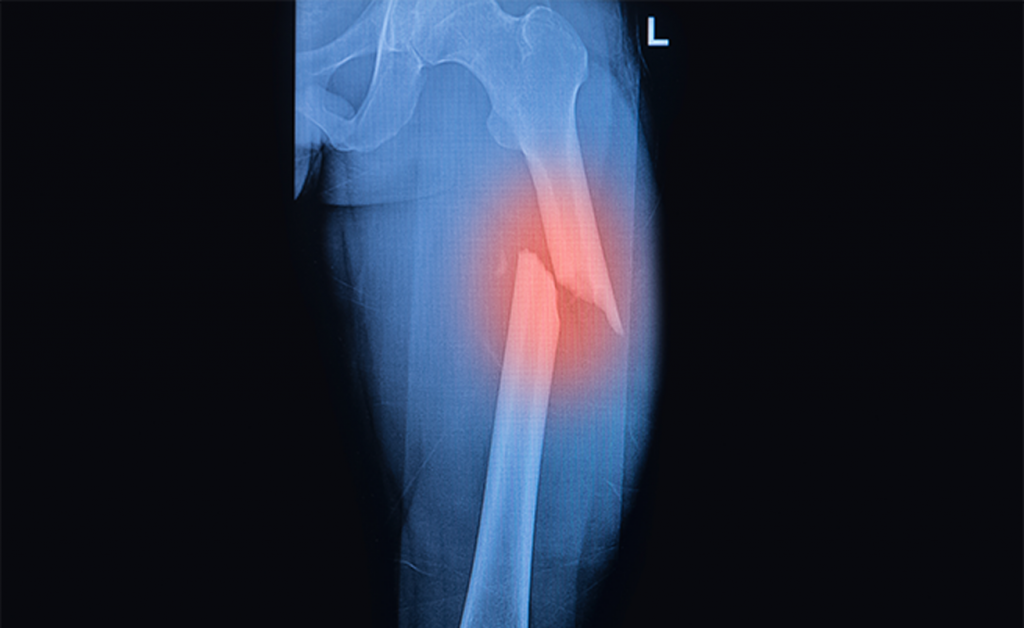

Tutti i rischi (come le fratture) delle cadute negli anziani

Tra i problemi clinici più seri degli anziani ci sono le cadute e l’equilibrio instabile, causa di elevati tassi di mortalità.

Anche se la maggior parte di queste cadute non causa lesioni fisiche importanti, circa il 5% provoca una frattura o richiede il ricovero. Inoltre, i tassi di cadute e le complicazioni associate aumentano sensibilmente con l’età e raddoppiano nelle persone con più di 75 anni non residenti in strutture di assistenza per anziani.

Le conseguenze di una caduta dipendono dal modo in cui si cade. Solitamente, gli anziani hanno riflessi rallentati e, quindi, meno protettivi in caso di cadute. Negli anziani le fratture più comuni sono:

Il problema delle cadute nella popolazione anziana non è legato alla maggiore incidenza, quanto piuttosto alla facilità con cui, a seguito di una caduta, si verifichi una lesione. Questo è conseguenza di un’elevata prevalenza di malattie che rendono particolarmente pericolose anche cadute lievi.